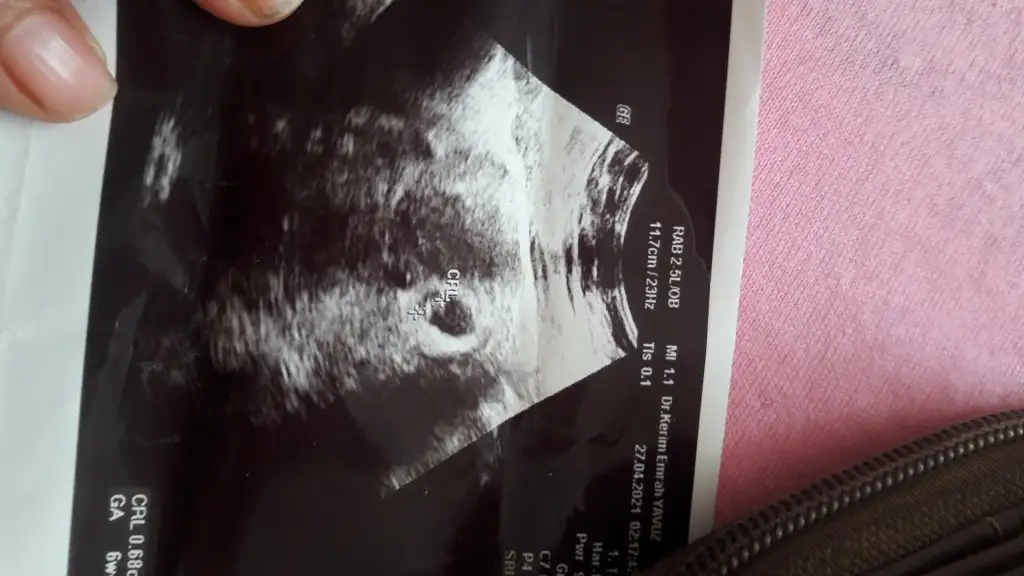

Merhaba arkadaşlar cinsiyet tahmini yapabilen var mı aramızda 🤗

11+4 görüntüleri ekliyorum . Merakla bekliyorum yorumlarimizi ..